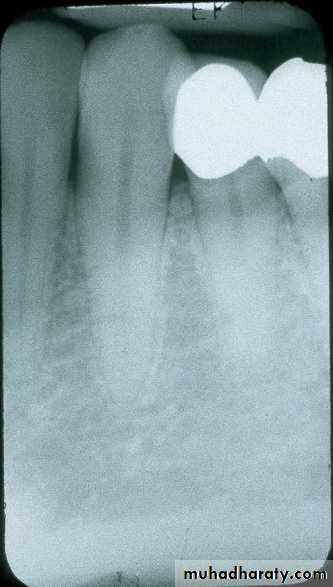

Mandibular Premolar

film equidistant from lingual surface of teeth (red arrows); film placed toward center of mouth, displacing tonguefront edge of film anterior to middle of canine; approximately centered on 2nd premolar

centered on second molar

Mandibular Molarfilm equidistant from lingual surface of teeth; in this case the film will usually contact lingual of molars